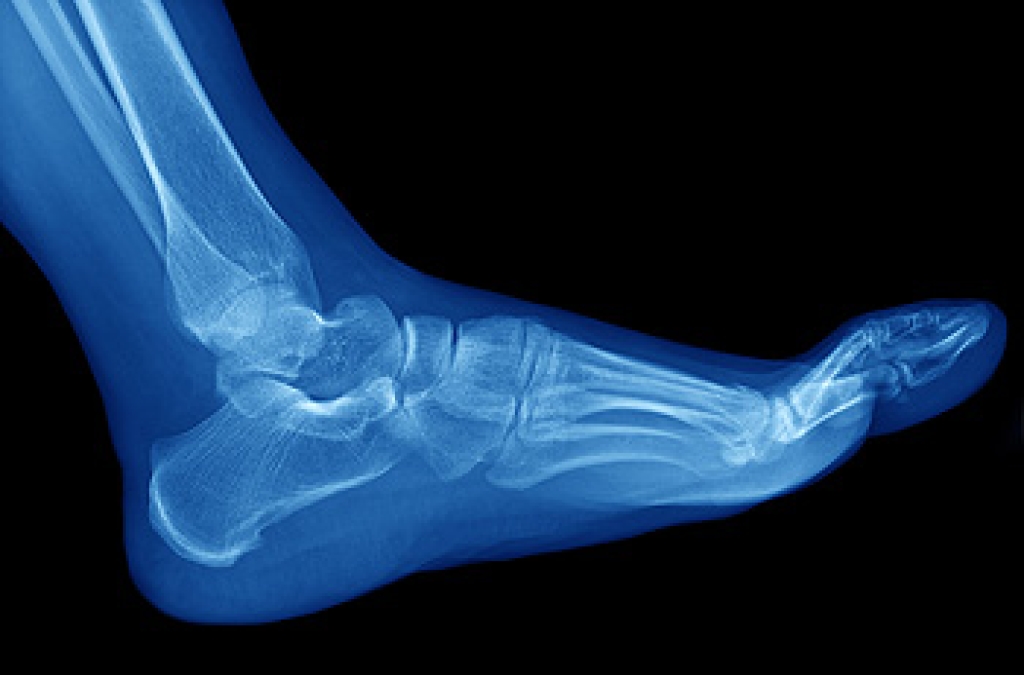

When it comes to foot injuries, understanding the types of broken bones in the foot is essential for effective diagnosis and treatment. Each foot contains 23 bones that may sustain an injury. A closed, or simple, fracture involves a break in the bone without piercing the skin. An open, or compound, fracture is more severe, where the bone breaks through the skin or is exposed due to a wound. This requires immediate medical attention due to the risk of infection. Greenstick fractures are commonly seen in children. These involve small, slender cracks in bones, as children's bones are more flexible. Hairline fractures, often called stress fractures, result from repetitive stress, particularly in activities like jogging or running. These tiny cracks frequently may occur in the long bones of the foot. Complicated fractures entail injuries to surrounding structures, such as veins, arteries, nerves, and the bone's lining, which may call for careful assessment and treatment. Comminuted fractures shatter the bone into small pieces, resulting in a slower healing process and requiring extensive care. Avulsion fractures occur when powerful muscle contractions pull pieces of bone where muscles attach to bones via tendons.

A broken foot is caused by one of the bones in the foot typically breaking when bended, crushed, or stretched beyond its natural capabilities. Usually the location of the fracture indicates how the break occurred, whether it was through an object, fall, or any other type of injury.